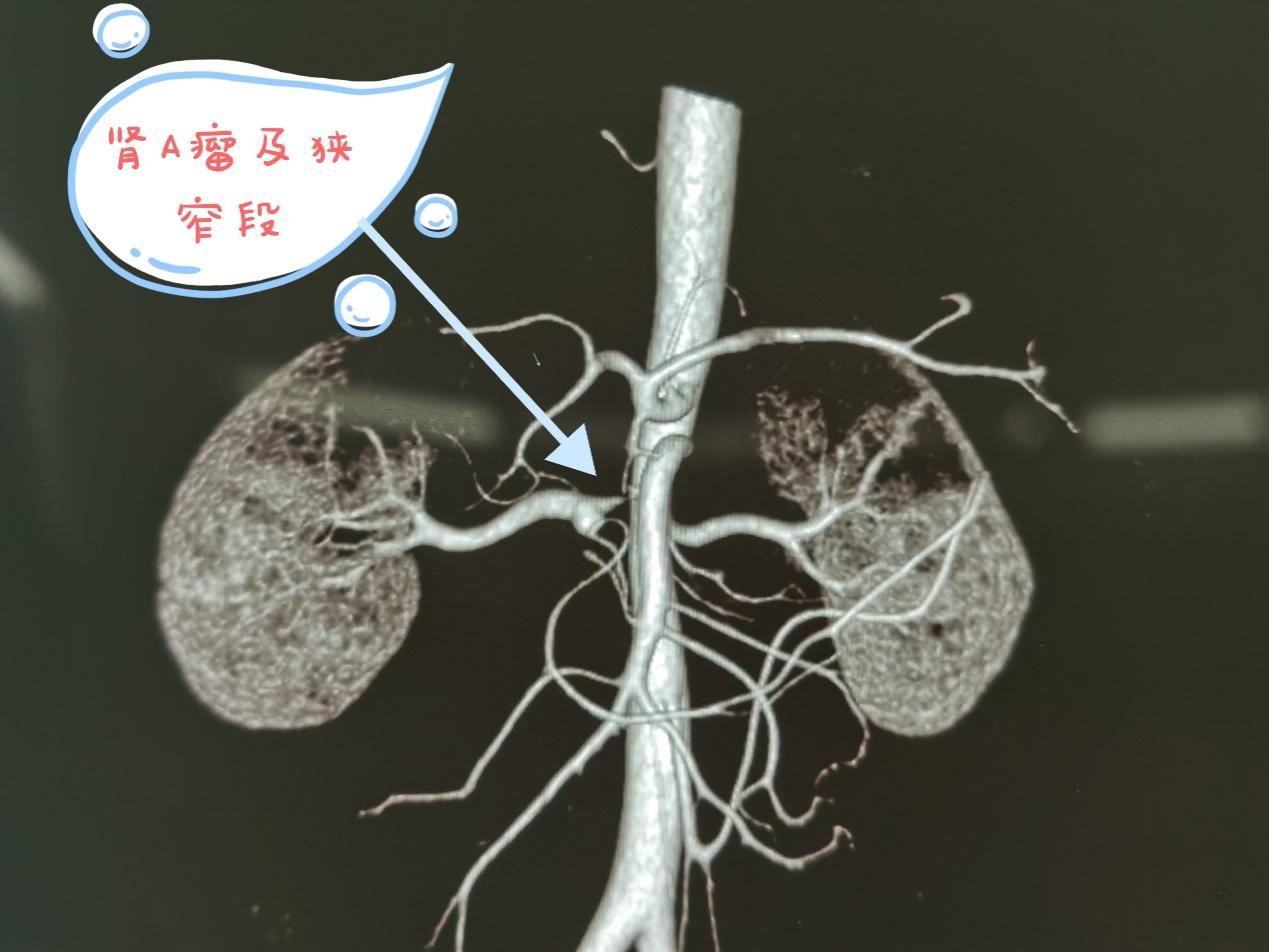

术前CTA

该患者因重度高血压出现晕倒,诊断右肾动脉狭窄并肾动脉瘤,狭窄率在90%以上,经院外介入治疗失败后到樱花动漫 泌尿外科就诊。了解病情后,泌尿外科柯昌兴主任联合李志鹏主任医师团队组织多学科MDT对患者的病情进行了详细的分析和讨论,并拟定了治疗方案。与患者和家属详细沟通后,在赵宁辉副院长的领导下,在医务处、OPO办公室协同心脏血管外科、麻醉手术科等团队的共同努力下,于2023年9月13日行“后腹腔镜右肾动脉瘤切除、右肾切取+腹膜外右髂窝自体肾移植术”,手术成功,术后血压恢复正常,术后5天彩超复查移植肾存活及功能正常,为患者解决了病痛。